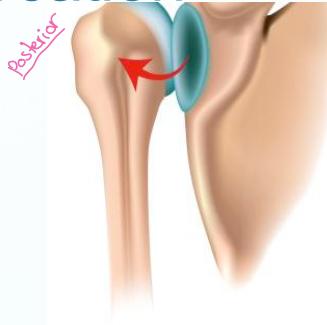

Posterior Shoulder Dislocation

Definition: The humeral head lies behind the glenoid

- Indirect force producing marked (internal rotation & adduction)

- Convulsion, with an electric shock

- Direct fall on elbow with shoulder internally rotated